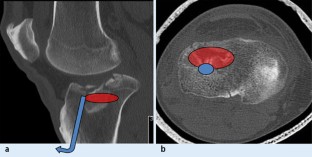

Abb. 1

This article reports on an innovative treatment concept to address split depression fractures (Schatzker type II) and depression fractures (Schatzker type III) of the tibial head using the balloon osteoplasty technique for fracture reduction.

Using the balloon technique achieves a precise and safe fracture reduction. This internal osteoplasty combines a minimal invasive percutaneous approach with a gently rise of the depressed area and the associated protection of the stratum regenerativum below the articular cartilage surface. This article lights up the surgical procedure using the balloon technique in tibia depression fractures.